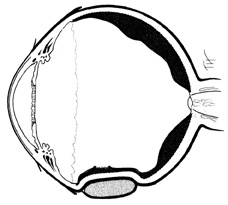

The anteroposterior position of the encircling element depends on the location of the vitreoretinal pathology to be supported. When retinal breaks in detached retina are associated with traction, the buckle should be positioned so that the posterior edge of the break lies on the posterior crest of the buckle. The buckling effect should extend for 30° on either side of the tear and extend anteriorly to the ora serrata (Fig. 20). If the encircling element is supporting pathologic conditions in attached retina, such as a retinal break, lattice degeneration, or prominent vitreoretinal adhesions, the most posterior aspect of the condition needs to be supported by the encircling element. If no specific pathologic factor is to be supported, the encircling element should support the posterior margin of the vitreous base.

Fig. 20. Correct position of buckle for flap retinal tear.